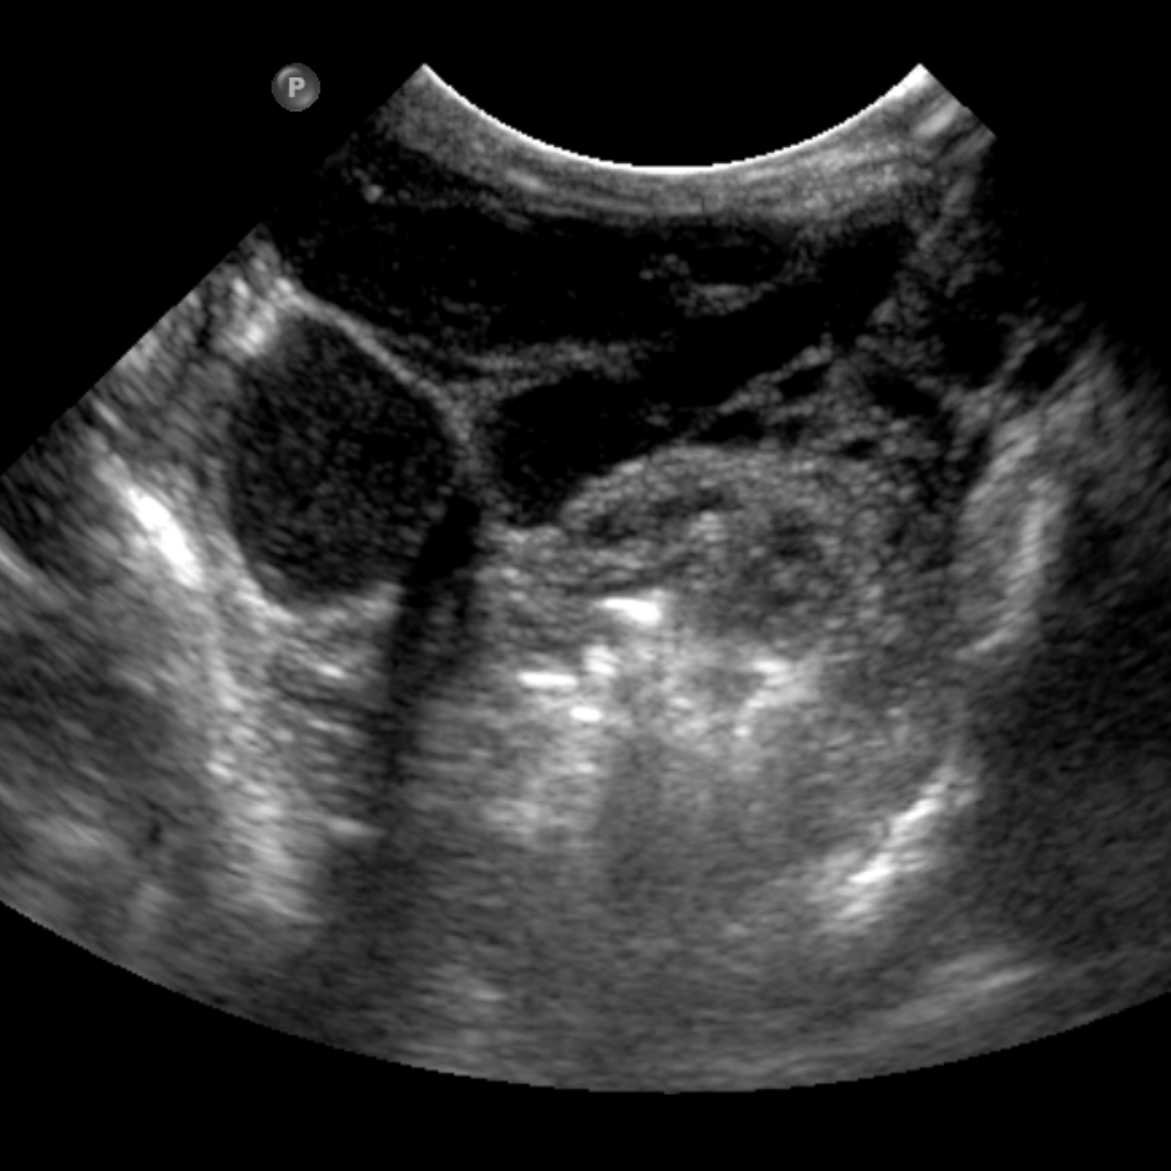

MRI of small LM cysts (top), US of needle injecting individual cysts (left), photo of US guided technique for small cyst puncture (right).